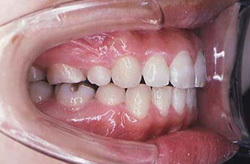

別名が(出っ歯)とも言われ、見た目に上の歯が前につき出ている噛み合わせを上顎前突と言います。

顎の骨に問題がある場合と、歯だけ前に出ている場合とがあります。下顎骨が小さいことが原因とする上顎前突が約70%であるとの報告があります。 うまく噛むことができません。転倒すると歯や骨を折ったり、唇を切ったりする可能性が高く、見た目も良くありません。

上の歯が前に飛びでしているので、良く噛めない状態です。また、特に横顔を見ると上唇が突出して口元の出っ張りが著しく目立っています。普段は口が閉じられません。無理をして口を閉じると口の回りやあごの部分の筋肉が緊張してこのようになります。

上の歯が前に飛びでしているので、良く噛めない状態です。また、特に横顔を見ると上唇が突出して口元の出っ張りが著しく目立っています。普段は口が閉じられません。無理をして口を閉じると口の回りやあごの部分の筋肉が緊張してシワができます。